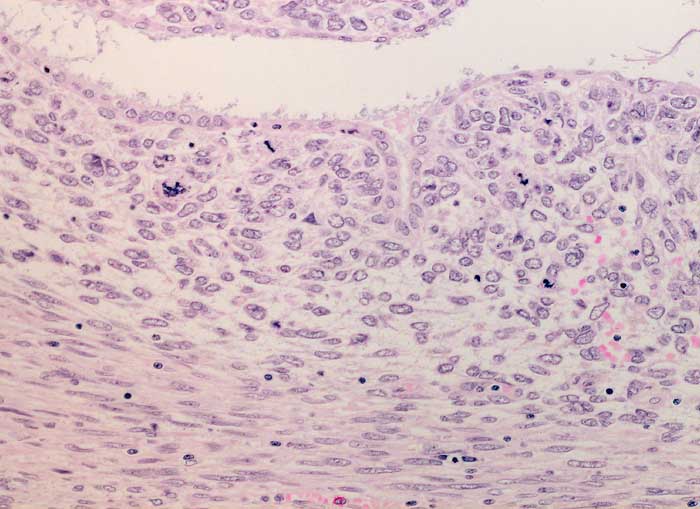

Adenosarkom

In diesem Bildausschnitt ist eine von gutartigem Epithel ausgekleidete Zyste erkennbar. Das angrenzende Stroma ist verdichtet (Kambiumschicht), weist ausgeprägte Atypien und mehrere, teils atypische Mitosen auf.

Postmenopausale Blutungsstörung, sonographisch suspekter Endometriumbefund, klinisch V.a. Endometriumkarzinom.

Histologie

200